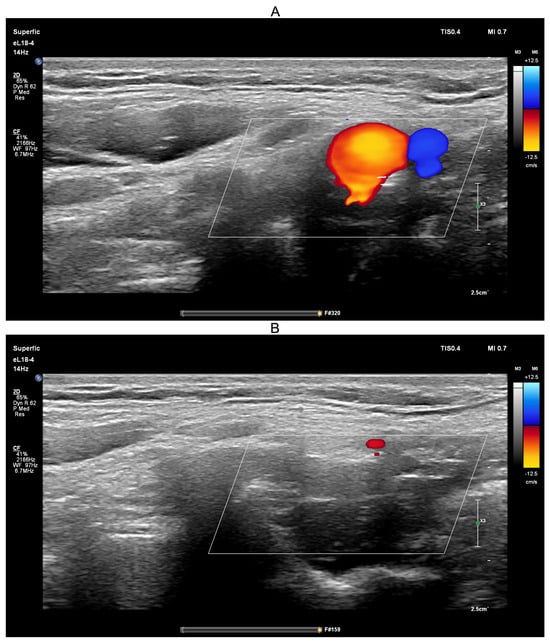

Ultrasound-guided compression of the common carotid artery was performed on a healthy volunteer in the upright position for approximately 10 s using the same PHILIPS EPIQ Elite ultrasound scanner (Figure 11).

The ultrasound-guided transient hypoemic/hyperemic response test was performed to confirm effective compression of the common carotid artery. Before compression (Figure 11A), red-coded blood flow in the common carotid artery and blue-coded blood flow in the jugular vein were clearly visible. During manual compression (Figure 11B), no color-coded flow was detected, confirming effective arterial occlusion. The procedure was conducted with the participant in the upright position, a physiological state in which jugular venous blood flow is minimal.

Figure 11. Screenshots from the PHILIPS EPIQ Elite ultrasound triplex scanner during the ultrasound-guided common carotid artery compression test (transient hypoemic/hyperemic response test). (A)—Before compression of the common carotid artery; (B)—During compression of the common carotid artery.